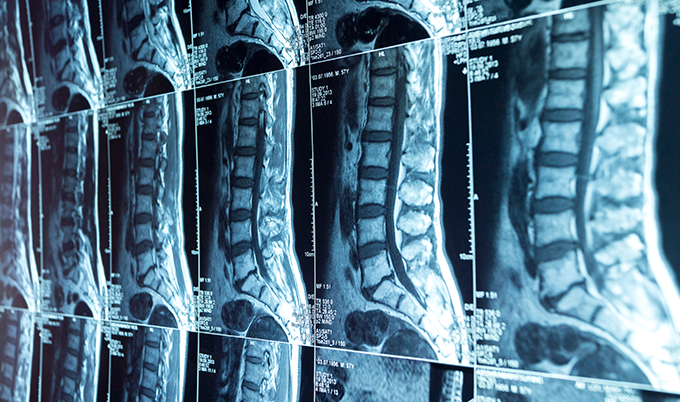

A cervical spine MRI uses magnetic fields and radio waves to create detailed 3D images of your neck’s soft tissues. These images reveal your spinal discs, spinal cord, nerves, and surrounding structures. Unlike X-rays that only show bones, cervical spine MRI imaging reveals herniated discs, spinal stenosis, tumors, and infections affecting the seven vertebrae in your neck. The scan typically takes 20-45 minutes. It requires no radiation exposure.

Herniated discs appear as bulging material protruding beyond normal disc boundaries on cervical spine MRI images. The C6-C7 level (between the sixth and seventh cervical vertebrae) experiences the highest herniation rates. C5-C6 follows closely behind.

Cervical spine MRI reveals whether stenosis results from herniated discs, thickened ligaments, bone spurs, or combinations of these factors. Radiologists grade stenosis severity using standardized systems. These measure cerebrospinal fluid space obliteration and spinal cord deformity.

Degenerative disc disease appears as signal intensity changes. Healthy discs appear bright on T2-weighted cervical spine MRI images due to high water content.

Degenerated discs show decreased signal intensity – appearing darker – as they lose hydration. Advanced degeneration includes disc height loss, bone marrow changes in adjacent vertebrae (Modic changes), and osteophyte (bone spur) formation.

The imaging plane determines the view. Sagittal images slice through your neck from right to left. They show all vertebrae in profile – ideal for assessing disc height and spinal alignment.

Axial images cut horizontally across your neck. They show spinal cord cross-sections and nerve root exits – perfect for evaluating stenosis and disc herniations. Coronal images provide front-to-back views. These are useful for detecting scoliosis or lateral abnormalities.